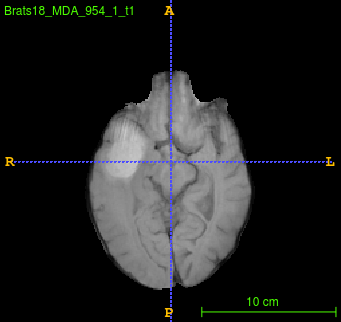

Segmentation of brain tumor from magnetic resonance imaging (MRI) is a vital process to improve diagnosis, treatment planning and to study the difference between subjects with tumor and healthy subjects. In this paper, we exploit a convolutional neural network (CNN) with hypercolumn technique to segment tumor from healthy brain tissue. Hypercolumn is the concatenation of a set of vectors which form by extracting convolutional features from multiple layers. Proposed model integrates batch normalization (BN) approach with hypercolumn. BN layers help to alleviate the internal covariate shift during stochastic gradient descent (SGD) training by zero-mean and unit variance of each mini-batch. Survival Prediction is done by first extracting features(Geometric, Fractal, and Histogram) from the segmented brain tumor data. Then, the number of days of overall survival is predicted by implementing regression on the extracted features using an artificial neural network (ANN). Our model achieves a mean dice score of 89.78%, 82.53% and 76.54% for the whole tumor, tumor core and enhancing tumor respectively in segmentation task and 67.90% in overall survival prediction task with the validation set of BraTS 2018 challenge. It obtains a mean dice accuracy of 87.315%, 77.04% and 70.22% for the whole tumor, tumor core and enhancing tumor respectively in the segmentation task and a 46.80% in overall survival prediction task in the BraTS 2018 test data set.